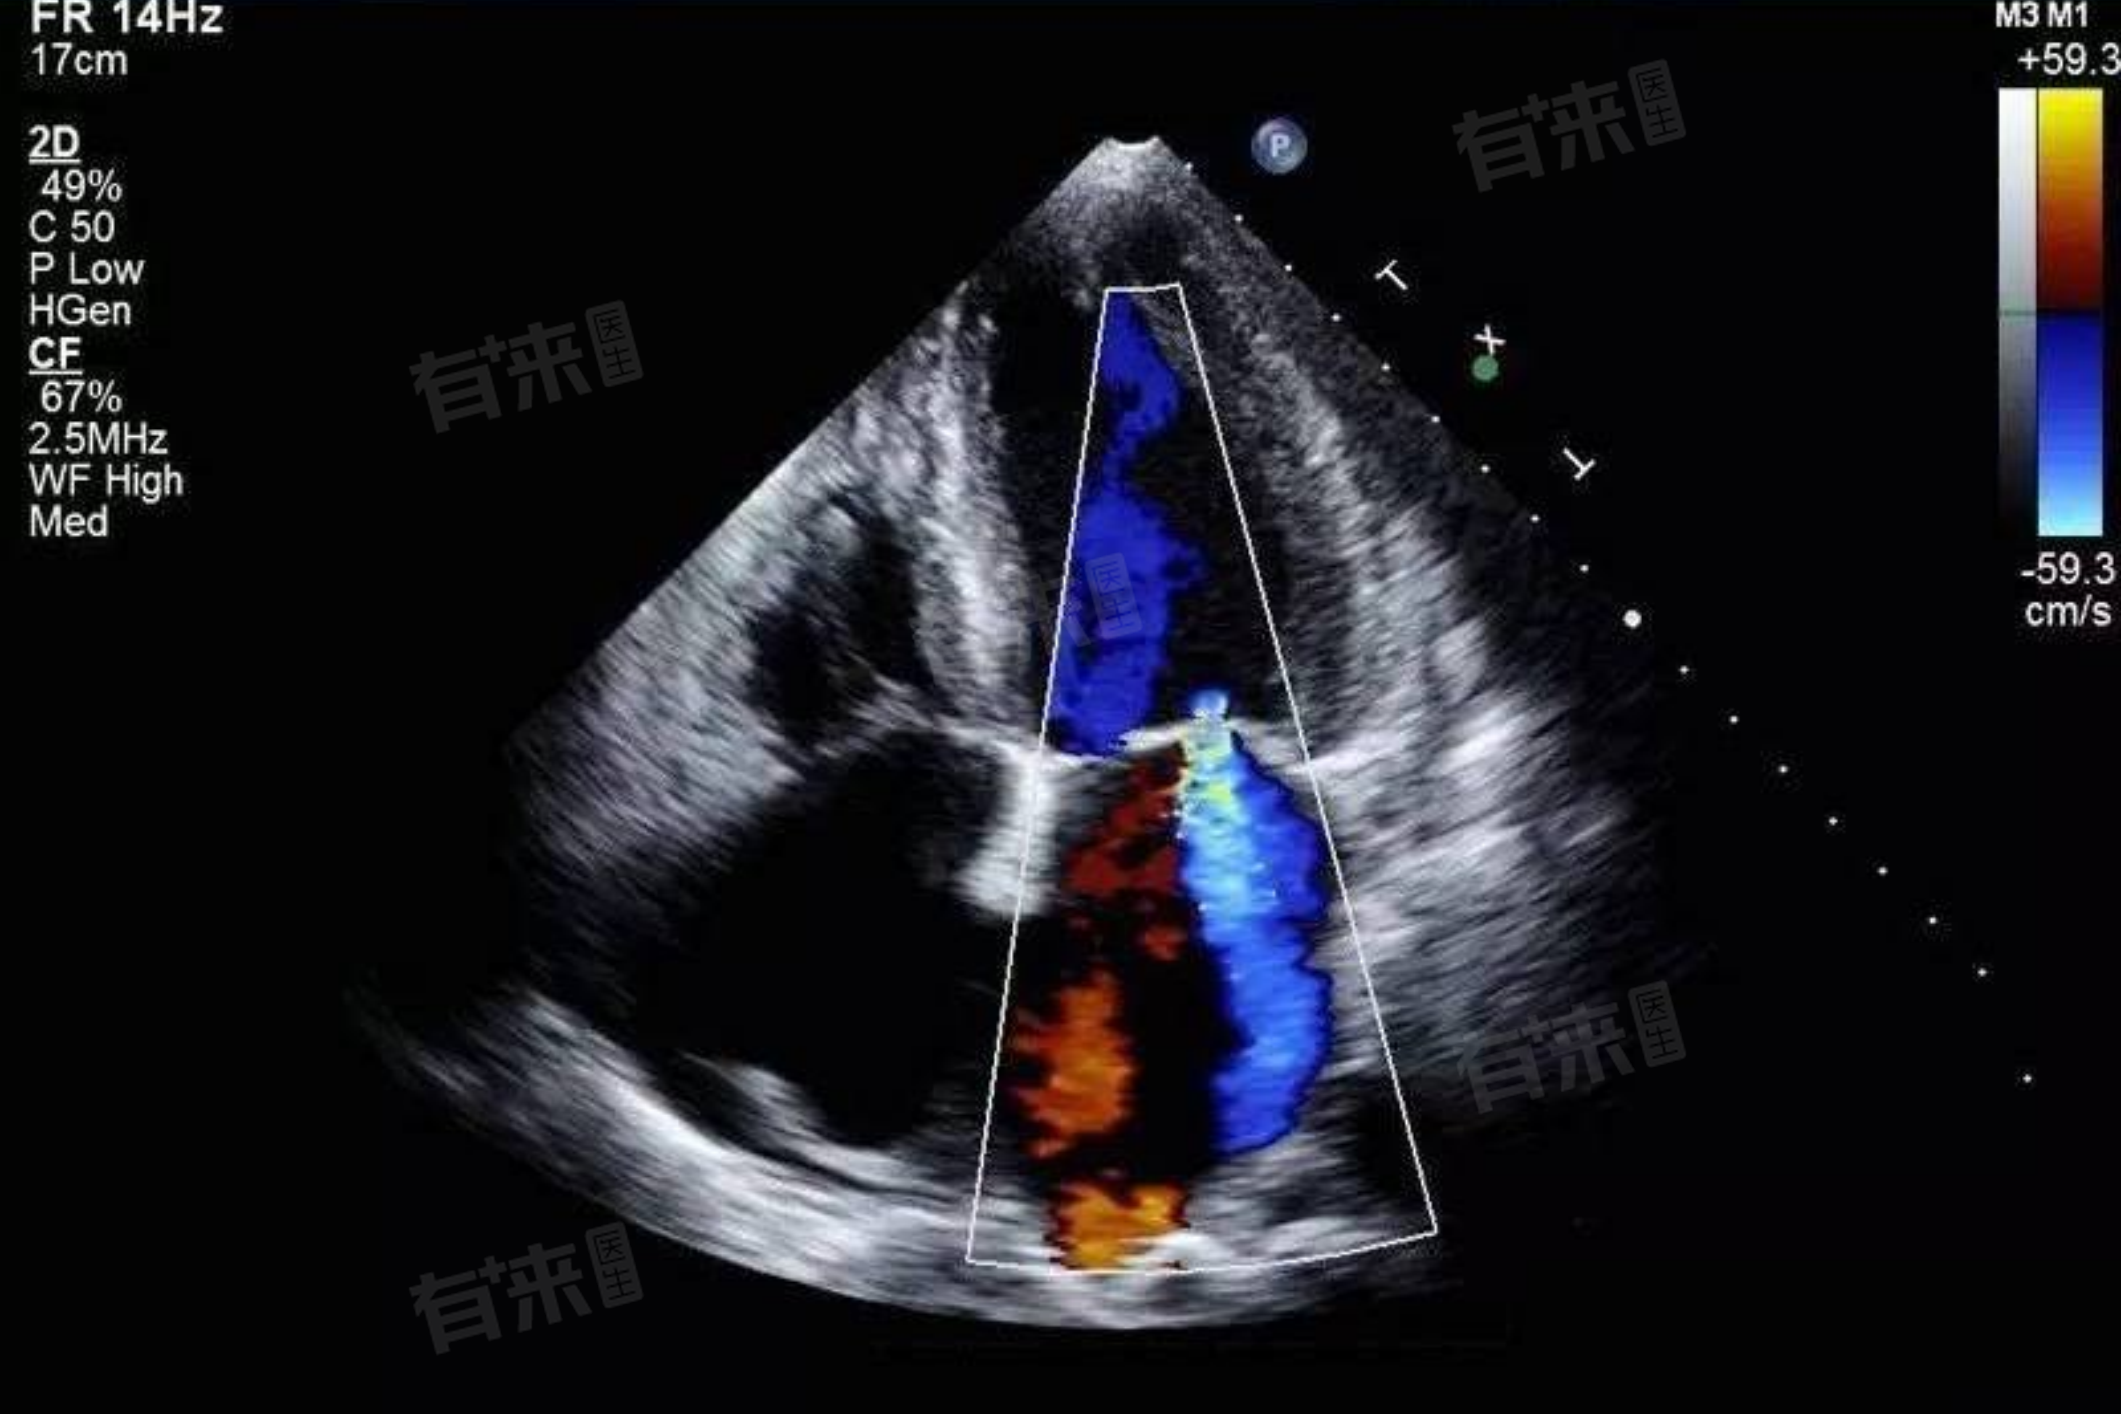

- 心脏彩超的功能:心脏彩超可以提供有关心脏的结构和功能信息,包括心脏的形态、大小、心室壁的运动和收缩功能等。它能够观察到心脏内部的结构变化,如心室壁的厚度、心腔的大小以及心脏瓣膜的功能状态。

- 辅助诊断:尽管心脏彩超不能直接确诊心梗,但它在心梗的诊断中具有非常重要的辅助作用。通过观察心室壁的动度、心脏的整体功能以及是否存在心肌室壁运动异常或心功能减退等间接指标,心脏彩超可以为医生提供有关心梗的线索。

- 评估心脏功能:在心梗发生后,心脏彩超可以评估心脏的整体功能状态,包括心脏的收缩和舒张功能。这对于判断心梗的严重程度以及制定后续治疗方案具有重要意义。